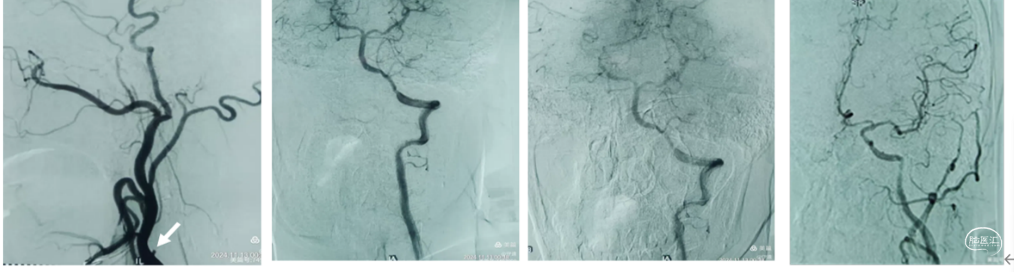

1、微导管到位:微导丝通过M1段艰涩困难,再次偿试通过M1段到达M2。携带微导管到达M2段,微导管造影显示远端有正向血流,在真腔内。下图1

2、支架释放:通过027微导管释放6X30mm 通桥蛟龙支架,静置5分钟后微造影,大脑中未显影,未见首过效应考虑血栓负荷较大。大脑前有血流。下图2

3、裸支架导丝技术:缓慢撤出微导管于体外,裸支架导丝,保留中间导管最大管腔。

4、中间导管收拢支架尾部一体回撤:中间导管跟进至M1段收拢支架尾部下,负压踹马桶抽吸中间导管,缓慢一体回撤支架和中间导管,一次取出长约3.5cm黯红色血栓。

5、二次抽吸清理:迅速清理导管进行二次抽吸未抽吸出肉眼血栓。

造影显示:

大脑中动脉畅通,远端血流达3级。但分叉以远分支似有少量血栓。考虑6x30m支架放置M2段过大,未再进行远端分支取栓,经导引导管给予替罗非班6ml推注。结束手术。